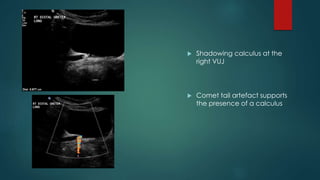

 80 year old female Non

specific flank pain.

Limited history due

patient's confusion



Right hydronephrosis

 Left ureteric jet present (i.e.

left ureter non obstructed)

 No ureteric jet on the right

(suspicious, although not in

itself diagnostic for ureteric

obstruction)

 Shadowing calculus at the

right VUJ

 Comet tail artefact supports

the presence of a calculus